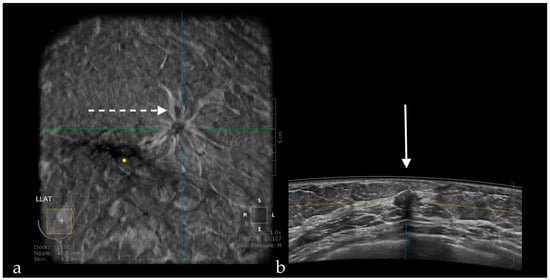

Insufficient Compression

In the case that the transducer is not evenly and sufficiently compressed, the air becomes interposed at the edges of the acquired image, hampering the analysis of the glandular parenchyma in the periphery of the image. Insufficient compression may also cause artifacts induced by Cooper ligaments, an artifact also found in the case of insufficient compression at HHUS (Figure 4). In order to reduce this artifact, the radiographer should perform an adequate compression.

Figure 4. The coronal plane (a) reveals a hypoechoic suspicious mass, also visible on the axial acquisition (b). Due to an inappropriate compression, the glandular tissue below the edge of the transducer cannot be appreciated (white arrow).